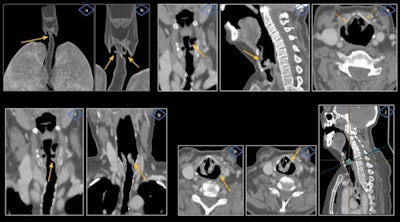

VCP is the loss of mobility of the true vocal cords secondary to a mechanical cause infiltrating the glottis or a neural lesion affecting the vagus or recurrent laryngeal nerves, and these nerves provide motor innervation to the intrinsic muscles of the larynx and travel a long distance from the skull base into the upper mediastinum, they explained.

"Most cases of VCP are unilateral due to a compressive mass, although up to a third may be bilateral," the researchers continued. "VCP can be classified in central or peripheral, with central causes being about 10%, and the vast majority are peripheral."

The cross-sectional imaging modality of choice is contrast-enhanced CT, and PET/CT may also have a role. The CT exam must include the upper mediastinum up to the aortopulmonary window and the scan should be acquired during a period of quiet respiration, so the cords are in an abducted position, the authors added.

VCP can be reliably identified on CT due to characteristic findings, although careful evaluation must be carried out by appropriately handling the scan planes of the glottis so potential pitfalls and mimics can be avoided.